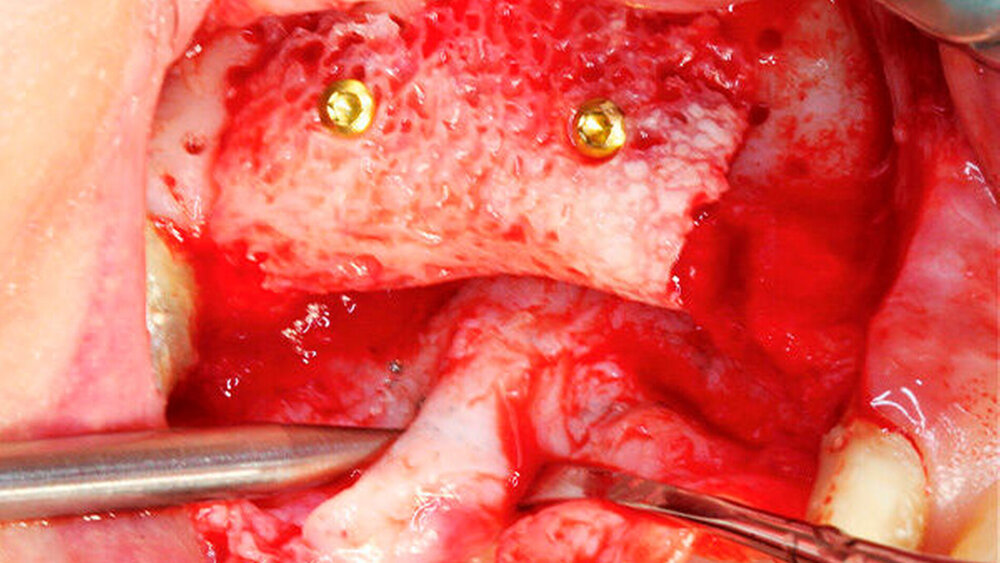

Die Schnittführung wurde nach dem Pillar-Sockel-Design (Blume) vorgenommen. Dabei liegt die Inzision weit im Vestibulum und verbindet zwei vertikale Entlastungsschnitte. Im Gegensatz zu der herkömmlichen krestalen Schnittführung bleibt das Periost über dem augmentierten Bereich damit völlig intakt. Nach der streng subperiostalen Präparation erfolgte die Kontrolle der Passung des CAD/CAM-Blocks. Ein ganz entscheidender Punkt ist, vor jeglichem Kontakt des Blockes mit Blut diesen in steriler Kochsalzlösung und am besten in der PRF-Flüssigkeit zu wässern, sodass sich keine Poren des Blocks mit Blutkoageln verschließen und innerhalb des Blocks ein nicht mit Blut gefüllter Hohlraum bildet. Vor der Befestigung des Blocks wurde die Kompakta des Empfängerbetts mit einer kleinen Kugelfräse mehrfach perforiert um sogenannte Bleeding Points zu setzen, die die Durchblutung des Knochenblocks gewährleisten. Mit zwei Osteosyntheseschrauben mit dem Durchmesser 1,5 mm und der Länge 9 mm wurde der allogene Knochenblock rotationssicher fixiert. Das Augmentat wurde mit einer dünnen Schweinepericard-Membran (Jason membrane, botiss biomaterials GmbH, Vertrieb Straumann) und der PRF-Membran abgedeckt. Der spannungsfreie Wundverschluss erfolgte mit der modifizierten vertikalen Matratzennaht nach Laurrell mit resorbierbarem Nahtmaterial (Vicryl 4.0). Postoperativ wurde ein Oberkiefer-DVT angefertigt. Die Nahtentfernung wurde im Rahmen der Nachsorgeuntersuchung sieben und 14 Tage postoperativ vorgenommen. Nach einer Heilzeit von sechs Monaten erfolgte die Implantation in Lokalanästhesie unter antibiotischer Abschirmung mit 2 g Amoxicillin oral eine Stunde präoperativ. Die Schnittführung erfolgte krestal, und nach subperiostaler Präparation wurde der Knochenblock dargestellt und die Osteosyntheseschrauben wurden entfernt. Danach wurden drei Implantate (Straumann) in den Knochenblock gesetzt und mit 0er-Verschlussschrauben abgedeckt. Die Wundrandadaptation erfolgte mit resorbierbarem Nahtmaterial, das bei der Verlaufskontrolle sieben Tage postoperativ vollständig entfernt wurde. Nach dreimonatiger gedeckter Einheilung wurden die Implantate im Rahmen einer Vestibulumplastik freigelegt. Dafür wurde eine erneute krestale Schnittführung regio 14 bis 17 vorgenommen und ein Splitflap präpariert. Der vestibuläre Wundrand wurde mit Einzelknopfnähten im Vestibulum fixiert. Im Bereich der Implantate wurde der Splitflap perforiert, um die Abdeckschrauben gegen Gingivaformer auszutauschen, und der Bereich des nun freiliegenden Bindegewebes wurde mit einer 3D-vernetzten Kollagenmatrix (mucoderm, botiss biomaterials GmbH, Vertrieb Straumann) abgedeckt. Diese wurde zunächst gewässert, um die Verarbeitung zu erleichtern, und an den Stellen der Gingivaformer gestanzt. Die Nahtentfernung erfolgte neun Tage postoperativ. (Abb. 1a bis 1f).

Ein 29-jähriger Patient stellte sich mit einer massiven Alveolarkammatrophie im rechten Unterkiefer in unserer Praxis vor. Diese lag in langen Jahren der Zahnlosigkeit begründet. Eine Beckenkammaugmentation kam für den Patienten nicht in Betracht. Dennoch wünschte er die Versorgung mit festsitzendem Zahnersatz. Nach ausführlicher Beratung entschied sich auch dieser Patient für eine Augmentation mit einem patientenindividualisierten allogenen CAD/CAM-gefertigten Knochenblock. Die DICOM-Daten des Unterkiefer-DVTs wurde an die Firma Zimmer gesendet, und es erfolgten wie im oben beschriebenen Fall eine virtuelle Planung und das virtuelle Design des allogenen Knochenblocks anhand der geplanten Implantatpositionen. Nach der üblichen Kontrolle und Freigabe des Chirurgen erfolgte die eigentliche Fertigung und Übersendung des Knochenblocks in die Praxis. Die Augmentation erfolgte auch in diesem Fall in Vollnarkose unter antibiotischer Abschirmung perioperativ mit Ampicillin. Die Schnittführung im Unterkiefer unterscheidet sich von der Sockelschnittführung im Oberkiefer aufgrund der Anatomie (N. mentalis). Auch bei diesem Patienten wurde eine tief im Vestibulum liegende bogenförmige Inzi‧sion durchgeführt, jedoch ohne die vertikalen Entlastungen. Nach streng subperiostaler Präparation erfolgte die Darstellung des N. mentalis. Die Vorbereitung des Spenderbetts sowie die Wässerung, Einpassung und Befestigung des allogenen Knochenblocks gestalteten sich wie im Fallbeispiel 1. Die Heilzeit des Knochenblocks dauerte ebenfalls sechs Monate. Zwei Implantate (Straumann) wurden nach krestaler Schnittführung in Lokalanästhesie eingebracht und heilten subgingival binnen drei Monaten ein. Aufgrund des massiven Volumenzuwachses war auch ebenfalls eine Vestibulumplastik im Zuge der Implantatfreilegung notwendig. Das Prozedere verlief ebenfalls wie im Fallbeispiel 1. Das freiliegende Gewebe wurde mit einer Kollagenmatrix abgedeckt. Dadurch konnte die Breite der befestigten Gingiva deutlich verbreitert werden.